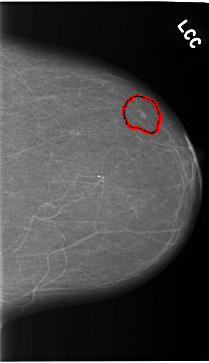

C_0119_1.LEFT_CC

LEFT_CC LINES 5808 PIXELS_PER_LINE 3336 BITS_PER_PIXEL 12 RESOLUTION 50 OVERLAY

FILE: C_0119_1.LEFT_CC.OVERLAY

TOTAL_ABNORMALITIES 1

ABNORMALITY 1

LESION_TYPE MASS SHAPE OVAL MARGINS CIRCUMSCRIBED

ASSESSMENT 4

SUBTLETY 3

PATHOLOGY MALIGNANT

TOTAL_OUTLINES 1

BOUNDARY